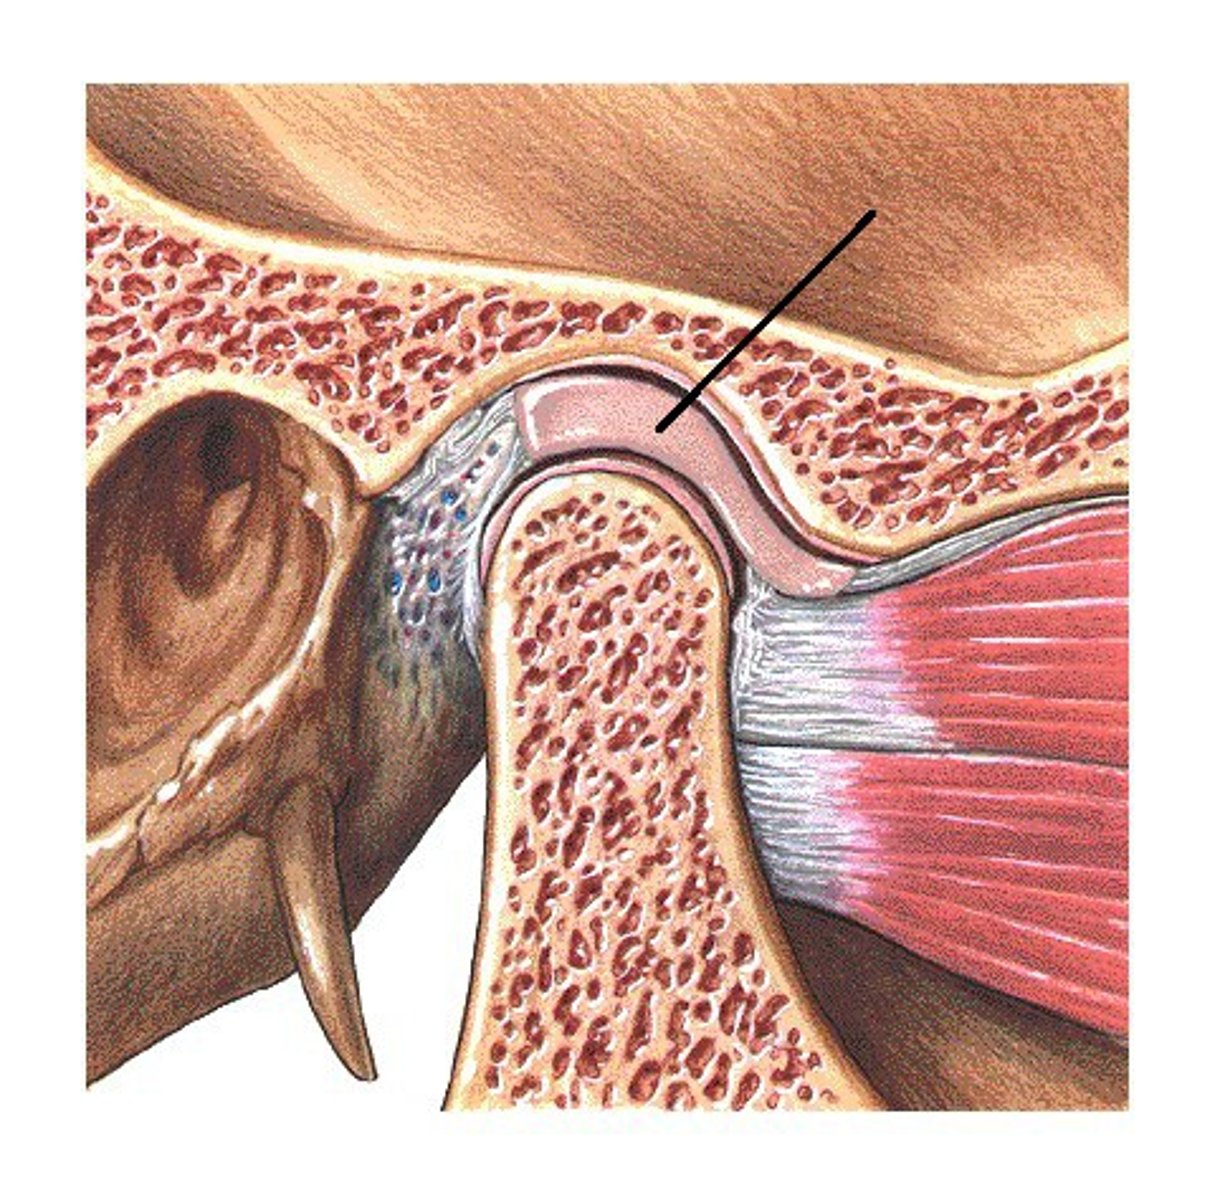

Articular capsule (temporomandibular joint)

Synovial membrane (temporomandibular joint)

articular disc (temporomandibular joint)